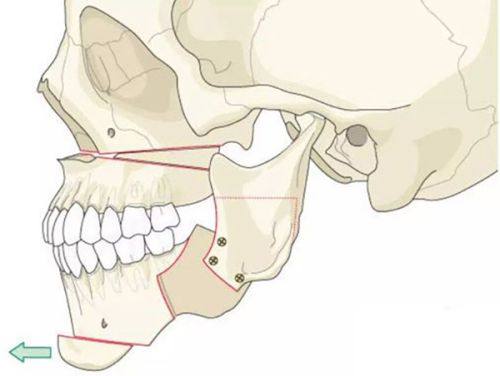

2. 地包天矫正:地包天不仅影响外貌,还会给患者的咀嚼和发音带来不便。尹泰镐院长针对地包天的矫正,会精良行详细的检查和诊断,确定是牙性还是骨性地包天。对于牙性地包天,通过牙齿矫正就可以有效解决;而对于骨性地包天,则需要结合正畸正颌联合治疗。他会在治疗过程中密切关注患者的情况,及时调整治疗方案,确保治疗成效达到至佳。